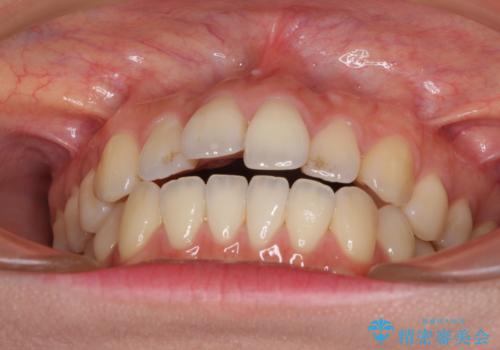

オープンバイトでかみにくい インビザラインによる矯正治療

- 前歯の上下スペースによる食べにくさを気にして来院された患者様です。

インビザラインにより上下の前歯の隙間を閉じていくこととしました。

上下の奥歯を圧下させるようにすることで、前歯を接触させるように計画しました。

上下の隙間に舌が入り込むことがオープンバイトの原因であったため、舌の筋肉のトレーニングも並行して行い、後戻りの抑制を図りました。